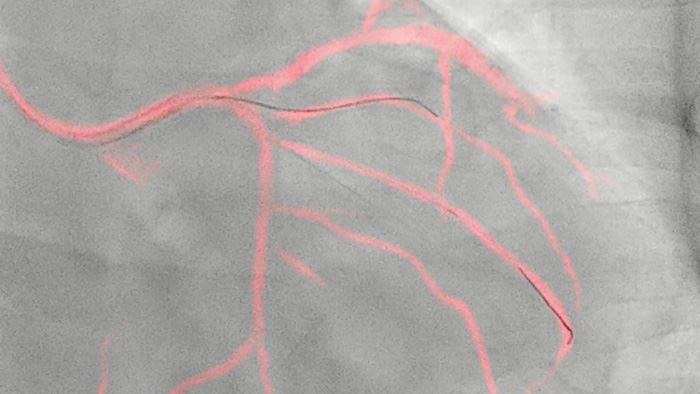

Esta tecnologia exclusiva da Philips cria uma visualização das artérias coronárias em tempo real e que compensa os movimentos. Um angiograma coronário destacado é sobreposto a uma imagem fluoroscópica 2D em tempo real, criando um mapa colorido que se ajusta automaticamente, fornecendo feedback visual contínuo sobre o posicionamento de fios e cateteres.